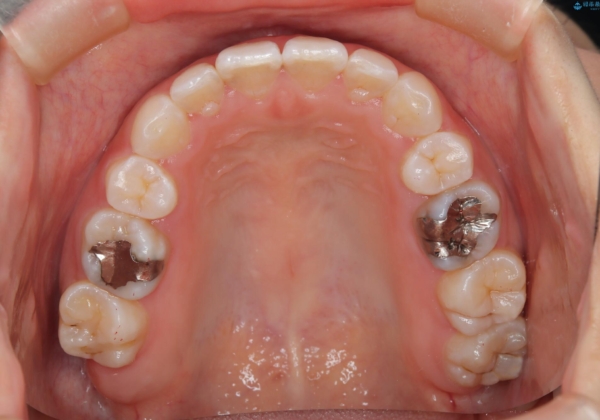

- 子供のころに矯正治療をされていたが、後戻りをしてしまったという20代女性の患者様です。上顎左右の2番が、咬合時に下顎の歯よりも内側に入っているクロスバイトという状態でした。奥歯の咬合関係は変えずに、マウスピース矯正にて前歯の並びを綺麗なアーチに仕上げました。再度後戻りしてしまうリスクを軽減させるために、リテーナー(保定装置)をお渡ししています。